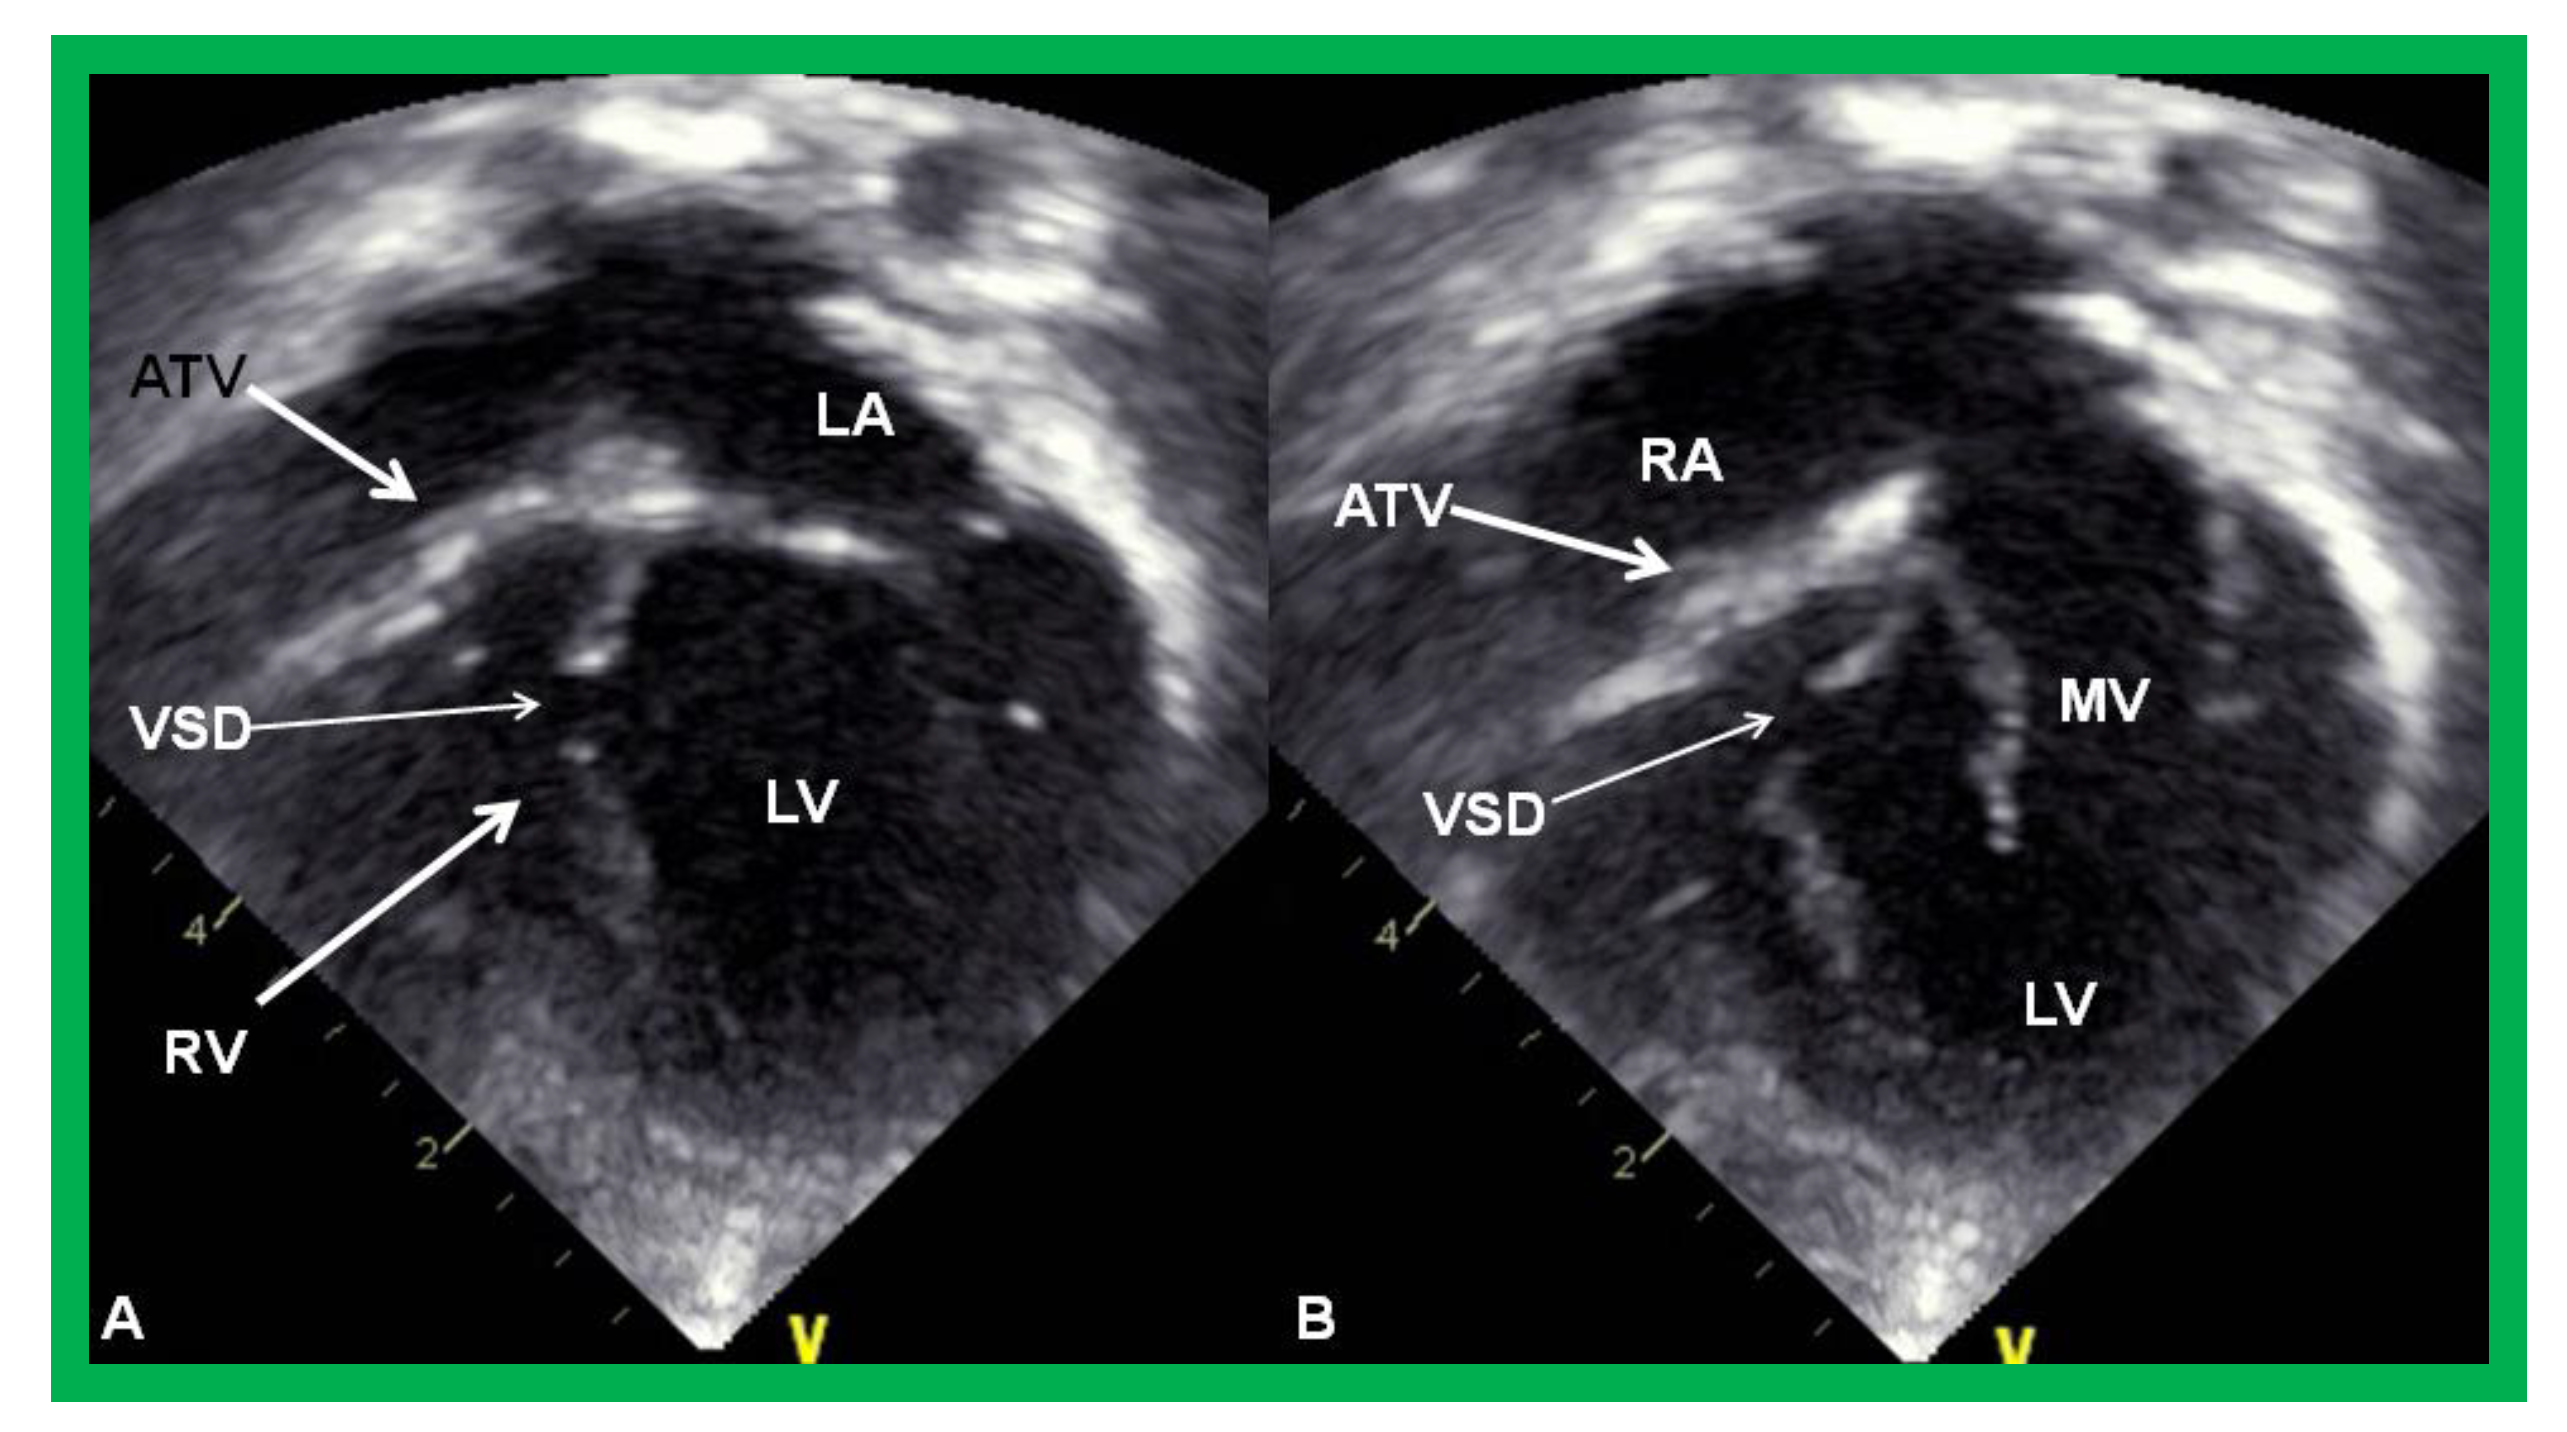

Figure 3.

Echocardiograms in apical four-chamber views of an infant with tricuspid atresia demonstrating a dilated left ventricle (LV), a small right ventricle (RV), and a dense band of echoes at the site where the tricuspid valve echo should be (ATV; thick arrow). Images with closed (A) and open (B) mitral valve are shown; the tricuspid valve remains closed in both situations. A ventricular septal defect (VSD; thin arrow) is also shown. LA, Left atrium; RA, Right atrium.